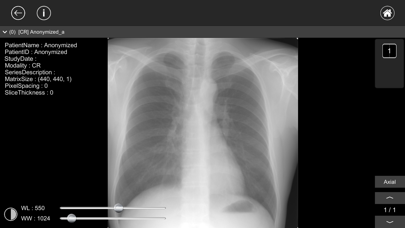

MR、CT、SPECT、PET、X線、超音波などで撮影された医用画像(DICOM画像)を閲覧することができます。

- ウインドウレベルの調整、画像の拡大・平行移動がタッチ操作で簡単に行えます。

※スクリーンショットで使用しているDICOMデータおよび患者名は架空のものです。

MR、CT、SPECT、PET、X線、超音波などで撮影された医用画像(DICOM画像)を閲覧することができます。

- ウインドウレベルの調整、画像の拡大・平行移動がタッチ操作で簡単に行えます。

※スクリーンショットで使用しているDICOMデータおよび患者名は架空のものです。